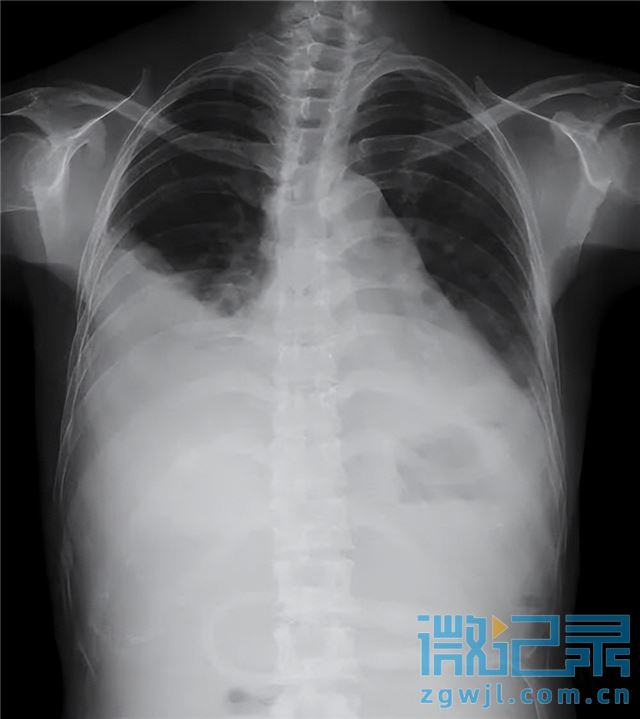

随着靶向治疗持续进行,联合中药扶正调理,姜奶奶的胸腔积液逐渐吸收,症状显著缓解:胸闷气促、咳嗽咳痰、恶心反酸等均明显减轻,食欲增加,体力恢复,活动耐量提升。治疗一周后,胸腔引流管顺利拔除。出院一月随访,复查显示右侧胸水完全吸收,左侧仅存少量包裹性积液,血常规、肝肾功能正常,患者整体状况良好,生活质量显著提高。